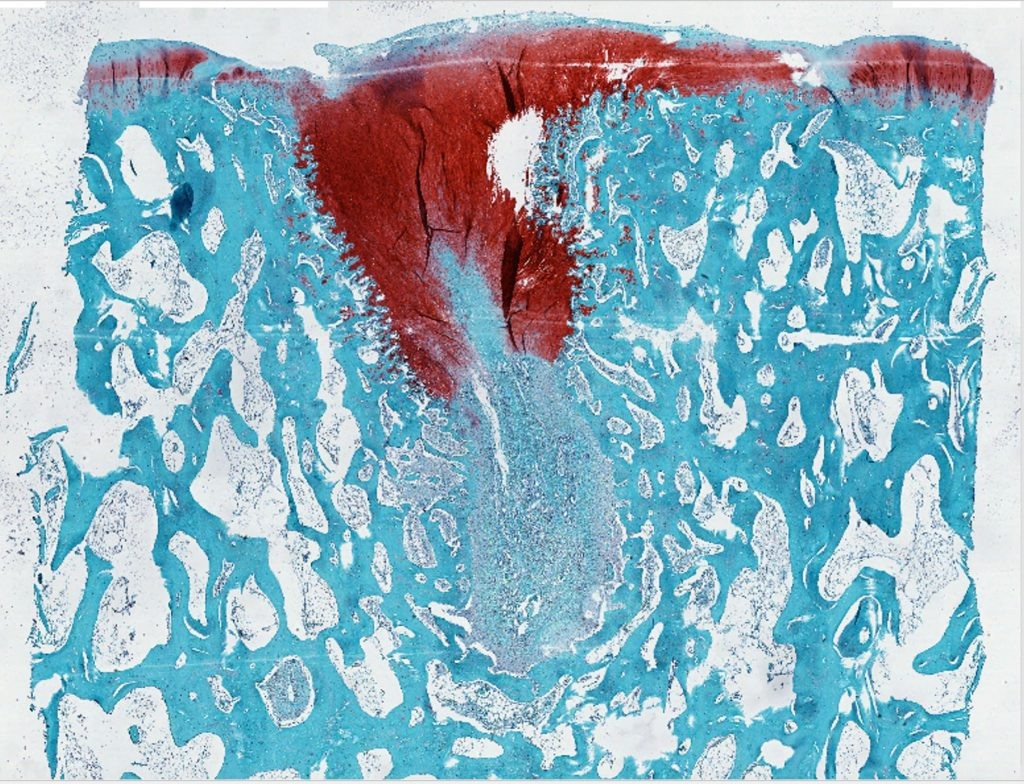

По мере постепенного разрушения каркаса в суставах животных формировался новый, высококачественный хрящ. При этом подвижность и другие свойства сустава были лучше, чем в контрольной группе. Анализ показал, что новый хрящ богат натуральными биополимерами, такими как коллаген II и протеогликаны, которые имеют решающее значение для безболезненной механической прочности суставов.

Обработанный хрящ с восстановлением дефекта. Изображение: Samuel I. Stupp, Northwestern University

На обложке: материал для восстановления хряща. Изображение: Samuel I. Stupp, Northwestern University